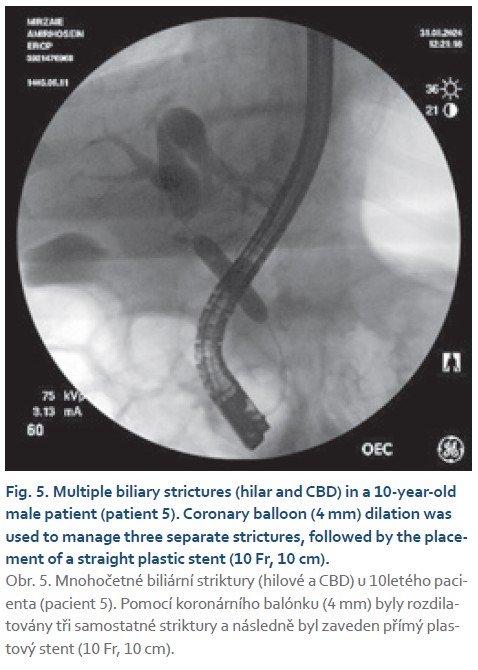

- patient 5: 10-year-old male with hilar and common bile duct (CBD) strictures;

- patient 5: three separate hilar and CBD strictures were navigated with coronary balloons, followed by straight plastic stent placement;